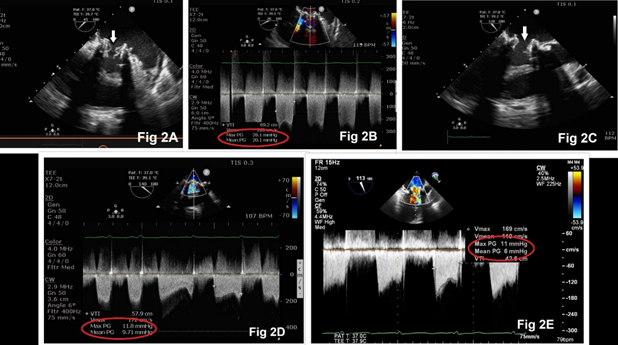

The estimated EuroSCORE II for a redo-valve surgery was high (10.01%). The ‘Heart-team’ suggested transcatheter mitral valve-in-valve replacement (TMViVR), and the patient’s informed consent was obtained. TMViVR was performed in a hybrid operating room under general anesthesia with all standard cardiac monitoring, including 3-D transesophageal echocardiography (TEE). A balloon-expandable 23 mm MyvalTM transcatheter mitral valve (Meril Life Sciences Pvt. Ltd., Vapi, Gujarat, India) was deployed by trans-septal puncture through the femoral route uneventfully (Fig. 1C, 1D, 1E). Anticoagulation therapy was commenced with intravenous unfractionated heparin followed by oral warfarin. On the third day of the procedure, the patient developed acute heart failure with severe breathlessness requiring intubation and mechanical ventilation. Soon, the patient developed cardiogenic shock requiring high-dose inotropes and vasopressors. A repeat TEE evaluation revealed buckling of the TMViV leaflets, leading to incomplete opening of the valve, causing severe MS with transvalvular gradient of 28.1/20.1 mmHg (peak/mean, Fig 2A, 2B). The patient was again wheeled into the operating room and balloon re-expansion of the TMViV was performed (Fig 2C). The hemodynamic parameters improved immediately with the reductions in transvalvular pressure gradient and inotropic/vasopressor support (Fig. 2D). Further course of the patient in the hospital was unremarkable. At one week, before discharge from the hospital, TTE showed normal functioning of the TMViV with a mean gradient of 6 mmHg, mild tricuspid regurgitation, and pulmonary artery systolic pressure of 36 mmHg (Fig. 2E). At a 3-month follow-up, the patient showed marked improvement in her symptoms and normal echocardiogram findings.

Figure 2: Transesophageal echocardiography demonstrating buckling of the mitral valve with high transvalvular gradient (Fig 2A, 2B). Re-expansion of mitral valve resulted in adequate mitral valve opening (Fig 2C) with reduction in valve gradient (Fig 2D, 2E).